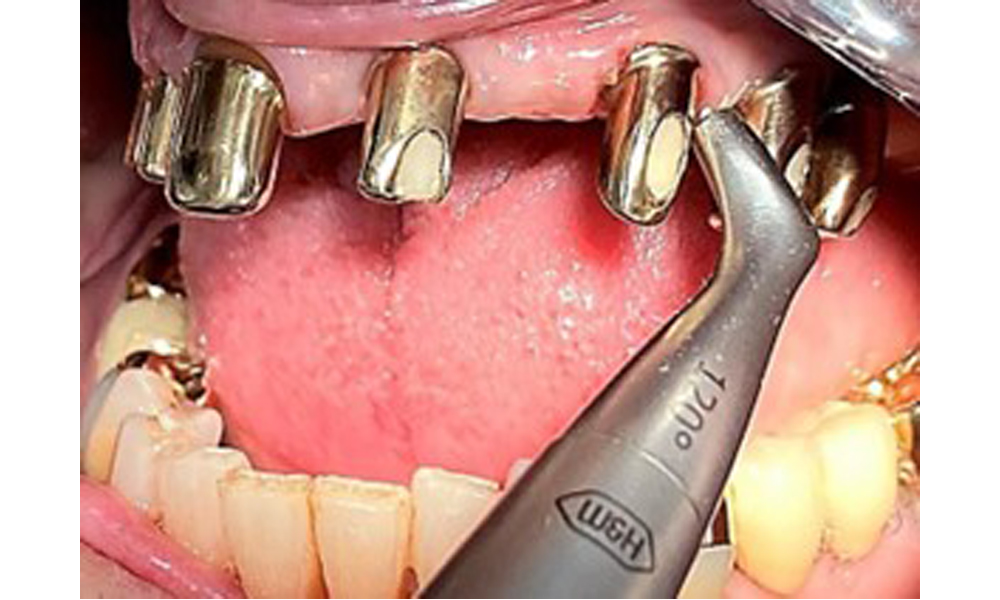

Die Patientin wurde vor über 25 Jahren mit einer kombinierten herausnehmbare Implantat-Teleskopprothese im Oberkiefer versorgt (Abb. 1, Abb. 2, Abb. 3) und ist sehr glücklich über ihren Zahnersatz. Im Unterkiefer hat die Patientin einen suffizienten festsitzenden Zahnersatz. (Abb. 4)

Der dentale Befund stellt sich wie folgt dar: Kombinierte herausnehmbare Implantat- und zahngetragene Teleskoparbeit auf Implantaten 15, 13, 21, 23, 24, 25 und Zahn 11 (Abb. 1, Abb. 2, Abb. 3). Im Unterkiefer ist die Patientin mit einem festsitzenden Zahnersatz versorgt. 37–34 sowie 45–47 haben suffiziente Brücken (Abb. 4). Kronenränder sind intakt, aktive kariöse Läsionen sind nicht vorhanden. An Zahn 43 zeigt sich eine Compositefüllung mit Randspalt. Im Unterkiefer liegen Rezessionen mit freiliegender Wurzeloberfläche zwischen 1 – 3 mm vor. Dies trifft auch für 11 zu.

Für die Entfernung von Zahnstein und Konkrementen am natürlichen Zahn kann Schall Ultraschall verwendet werden sowie konventionelle Handinstrumente (8). An den Implantaten sind für mineralisierte Beläge Titan- oder Kunststoffküretten (Abb. 10) einzusetzen oder ein Kunststoff- bzw. Peek-Ansatz (Abb. 11) für die Ultraschallbehandlung, um die Implantatoberfläche nicht zu beschädigen.